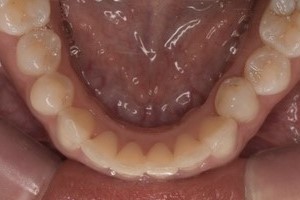

CASE 3

| 年齢・性別 | 30代・女性 |

|---|---|

| 主訴 | 定期検診 |

| 治療内容 | PMTC |

| 治療期間 | 60分 |

| 治療費 | 5,750円 |

| リスク・副作用 | しみる可能性があります。 |

| 治療方針 | PMTCでステインの除去。 |

| 担当者所見 | ステインが付きやすいため、3カ月毎の定期検診で除去する。 |